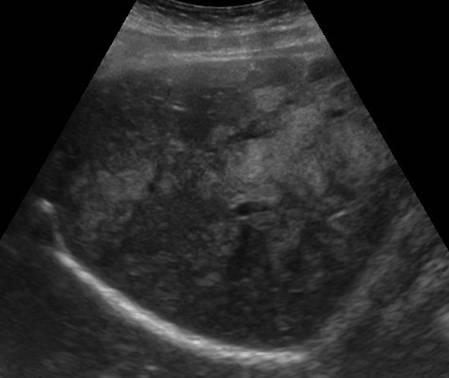

Gan nhiễm mỡ

» Thông tin: Nữ giới – 40 tuổi.

» Lâm sàng: Kiểm tra sức khỏe.